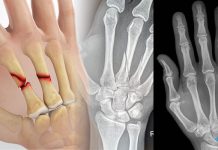

Rolando kırığı, başparmak metakarp kaidesinin eklem içi çok parçalı kırığıdır; “T” veya “Y” şeklinde olan tipleri ile karşımıza çıkar. Ayrılmamış kırıklarda alçı tespit için yeterliyken, ayrılmış kırıklarda açık redüksiyon internal fiksasyon tekniği kullanılmaktadır.